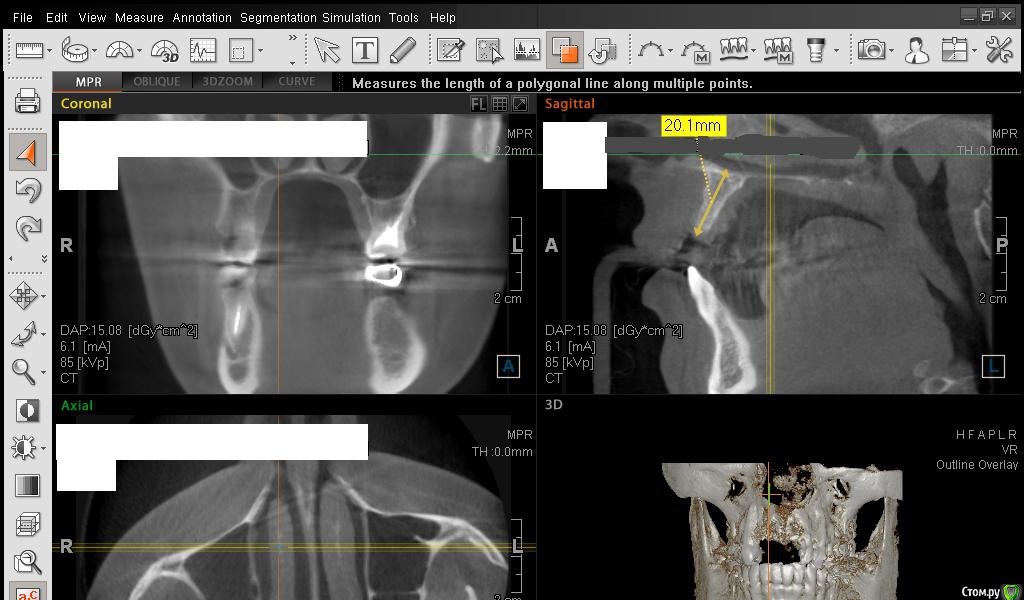

Сестричка Опубликовано 2 марта, 2015 Автор Поделиться Опубликовано 2 марта, 2015 Еще пара срезов Ссылка на комментарий

SDC Опубликовано 2 марта, 2015 Поделиться Опубликовано 2 марта, 2015 Интересны размеры беззубого альвеолярного отростка на самой вершине его или рядом с вершиной на расстоянии 1 мм. от нее в проекции будущего местоположения имплантатов.Желательно размеры проводить рядом с объектом (как в черчении)По-моему, диаметр 3 мм. подходит для имплантации без костной пластики, но без трансплантации десны, одномоментно с имплантацией, не обойтись. 1 Ссылка на комментарий

АнтонТЛТ Опубликовано 2 марта, 2015 Поделиться Опубликовано 2 марта, 2015 Сам крест еще нужно повернуть, чтобы было одна полоса креста была параллельна краю челюсти Ссылка на комментарий